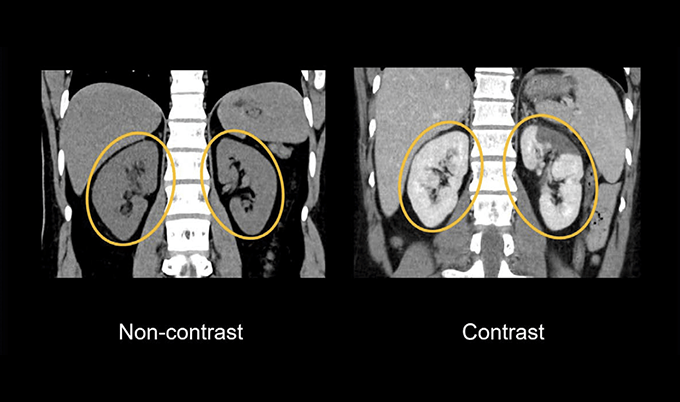

Soft tissue detail increases dramatically. Non-contrast CT shows organs as various shades of gray with subtle density variations. The liver, spleen, and pancreas blend together with similar gray tones. Add contrast, and each organ enhances at different rates and intensities, creating clear boundaries. The pancreas appears distinctly different from the liver, making it possible to detect small abnormalities that would otherwise hide in the uniform grayness.

Vascular structures become visible or invisible. Without contrast, major blood vessels appear as slightly darker structures within organs. You can see the largest arteries and veins, but smaller vessels disappear into surrounding tissue. With contrast, the entire vascular tree illuminates. Radiologists can trace blood vessels down to surprisingly small branches, identify narrowing or blockages, and detect aneurysms that would be completely invisible without contrast.

Tumor detection sensitivity changes substantially. Small tumors often share similar density to surrounding normal tissue. On non-contrast scans, these lesions might be invisible or so subtle that radiologists report “indeterminate findings.” Contrast reveals these tumors in two ways – through their distinct enhancement pattern compared to healthy tissue, and by showing their blood supply, which differs from normal anatomy.

Diagnostic confidence shifts from uncertain to definitive. Non-contrast imaging often results in reports containing phrases like “possible mass,” “cannot exclude,” or “recommend further evaluation with contrast.” Contrast imaging more frequently produces definitive diagnoses – “appendicitis confirmed,” “no evidence of pulmonary embolism,” or “metastatic disease identified.” This certainty prevents diagnostic delays and unnecessary follow-up testing.